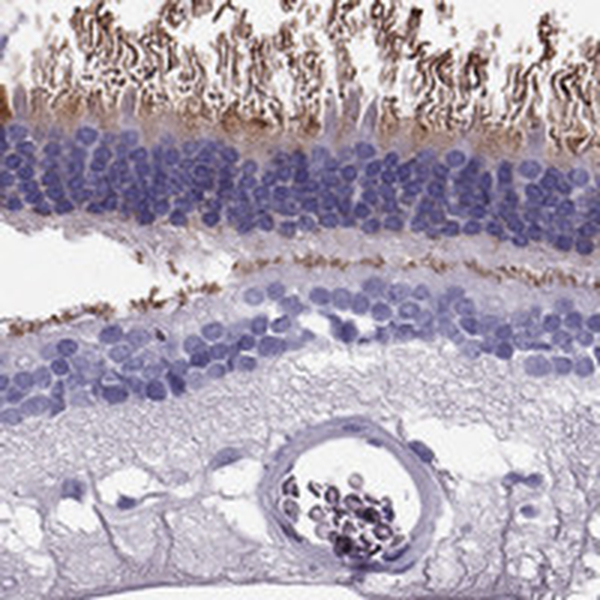

Immunohistochemical staining of human cerebral cortex, endometrium, eye, retina and liver using Anti-PDE6A antibody HPA016970 (A) shows similar protein distribution across tissues to independent antibody HPA074677 (B).